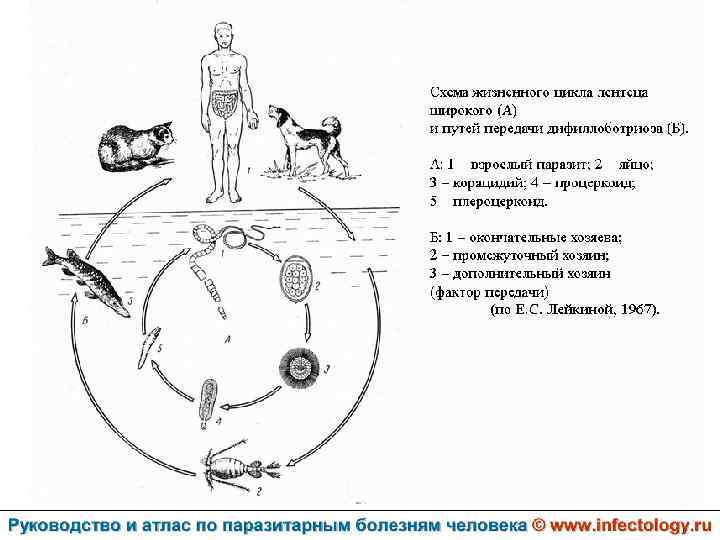

Дифиллоботриоз (шифр по МКБ 10 – B 70. 0) – зоонозный биогельминтоз с хроническим течением, характеризующийся нарушением функций верхнего отдела пищеварительного тракта, а при тяжелом течении - развитием анемии.